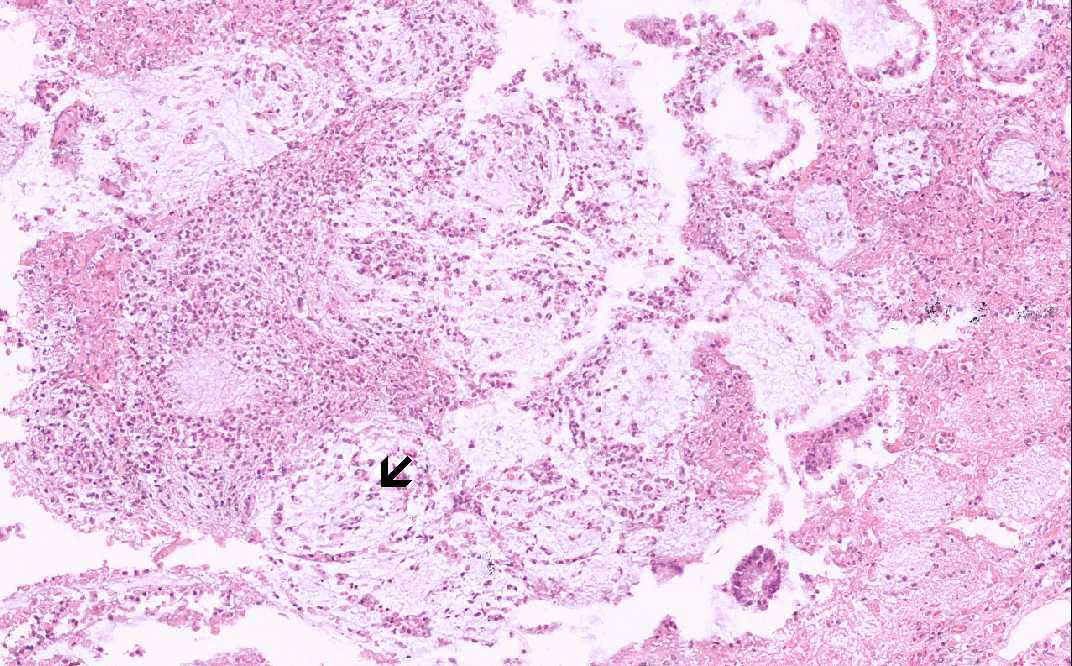

Area 3: Note the interesting linear arrangement of the inflammatory cells and the mucin (arrow).

• The submucosa (S) is rather edematous and the organization appears loose. The mucosa is rather irregular and is coated by a layer of inflammatory and necrotic substance. There is also patchy necrosis of the superficial aspect os of the mucosa. In the smaller lesions, the affected crypts become dilated and exude an inflammatory and necrotic substance reminiscent of a erupting volcano or mushroom-like structure (Area 1). There is extensive loss of colonic glands due to the necrosis. In the more severely affected areas, the inflammatory and necrotic substance  fuses together to form a pseudomembrane (Area 2). This pseudomembrane extends laterally to overlie adjacent normal appearing mucosa. The exudate is composed largely of karyorrhectic debris and neutrophils. Also the mucin has a tendency to alig with the necrotic debris and neutrophils in an interesting linear arrangement (Area 3).